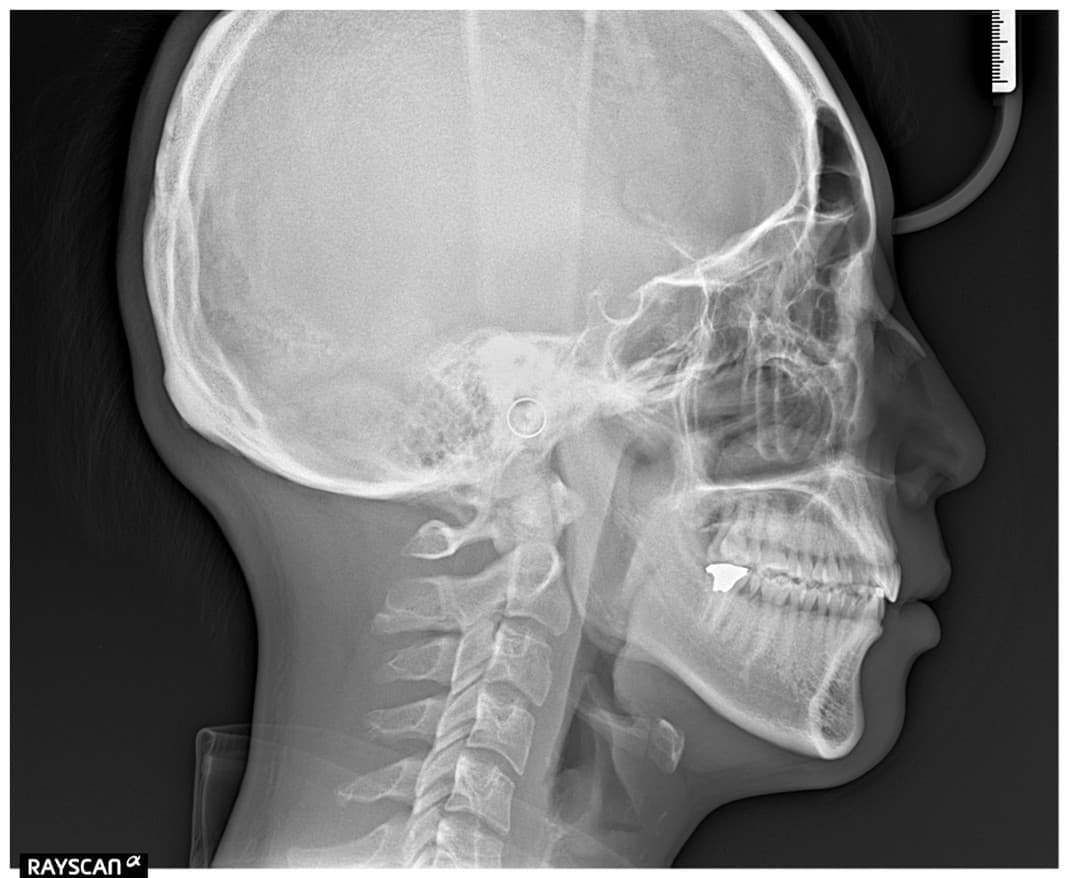

最新CTスキャナー導入

以前から院長とは話題に上がっていたのですが、「とにかく常に最高の治療を目指したい」という目標を達成するため、このたび最新のCTスキャナーを導入いたしました。

最新機器の特徴ですが

画像の解像度はさらに精密になり、

一度に撮影できる範囲も非常に広く、

技術の進化のおかげで被ばく量もまったく気にならないレベル。

正直、「すごいやつ」です。